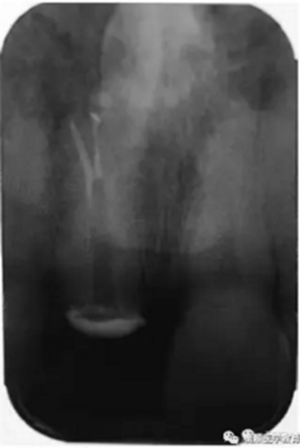

基于臨床檢查和X線片顯示,診斷為右上頜中切牙根尖周炎伴額外牙。治療計(jì)劃是先行患牙的根管治療,制作臨時(shí)義齒,最后制作樁核冠。應(yīng)用橡皮樟和顯微根管技術(shù),利用ProTaper旋轉(zhuǎn)銼配合使用 Hedstrom 銼和桉葉油,將根管內(nèi)充填物取出,觀察X線片可見(jiàn)根尖三分之一處主根管一分為二,確定另一根管的工作長(zhǎng)度,兩根管同行常規(guī)根管治療,充填后X線片顯示根管充填良好。樁核冠修復(fù)1年后,患牙無(wú)疼痛,影像檢查發(fā)現(xiàn)根尖顯影正常,根尖疾病治愈。

圖2. 患牙根管充填后即刻X線片顯影